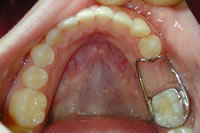

When a primary tooth is lost prematurely the teeth can drift into the new space crowding out the permanent tooth that is supposed to erupt into that space in the future. A space maintainer keeps baby teeth from shifting into the space where the tooth was lost so the permanent tooth can erupt in its natural proper space. As the permanent tooth erupts, Dr. Sidorwill remove the appliance. Space maintainers can help eliminate the need for extensive orthodontics in the future.

band loop space maintainer

erupting tooth